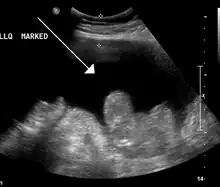

Ultrasound investigation is often done before attempts to remove fluid from the abdomen. This may reveal the size and shape of the abdominal organs, and Doppler studies may show the direction of flow in the portal vein, as well as detecting Budd–Chiari syndrome (thrombosis of the hepatic vein) and portal vein thrombosis. The sonographer also can estimate the amount of ascitic fluid, and difficult-to-drain ascites may be drained under ultrasound guidance. An abdominal CT scan is more accurate than a sonogram to reveal abdominal organ structure and morphology.[12]